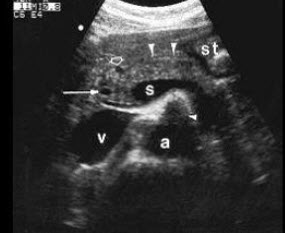

根据以下肝超声检查声像图,诊断为()

A.肝癌并门脉癌栓

B.肝硬化

C.脂肪肝

D.肝炎

E.血吸虫性肝硬化并门脉血栓